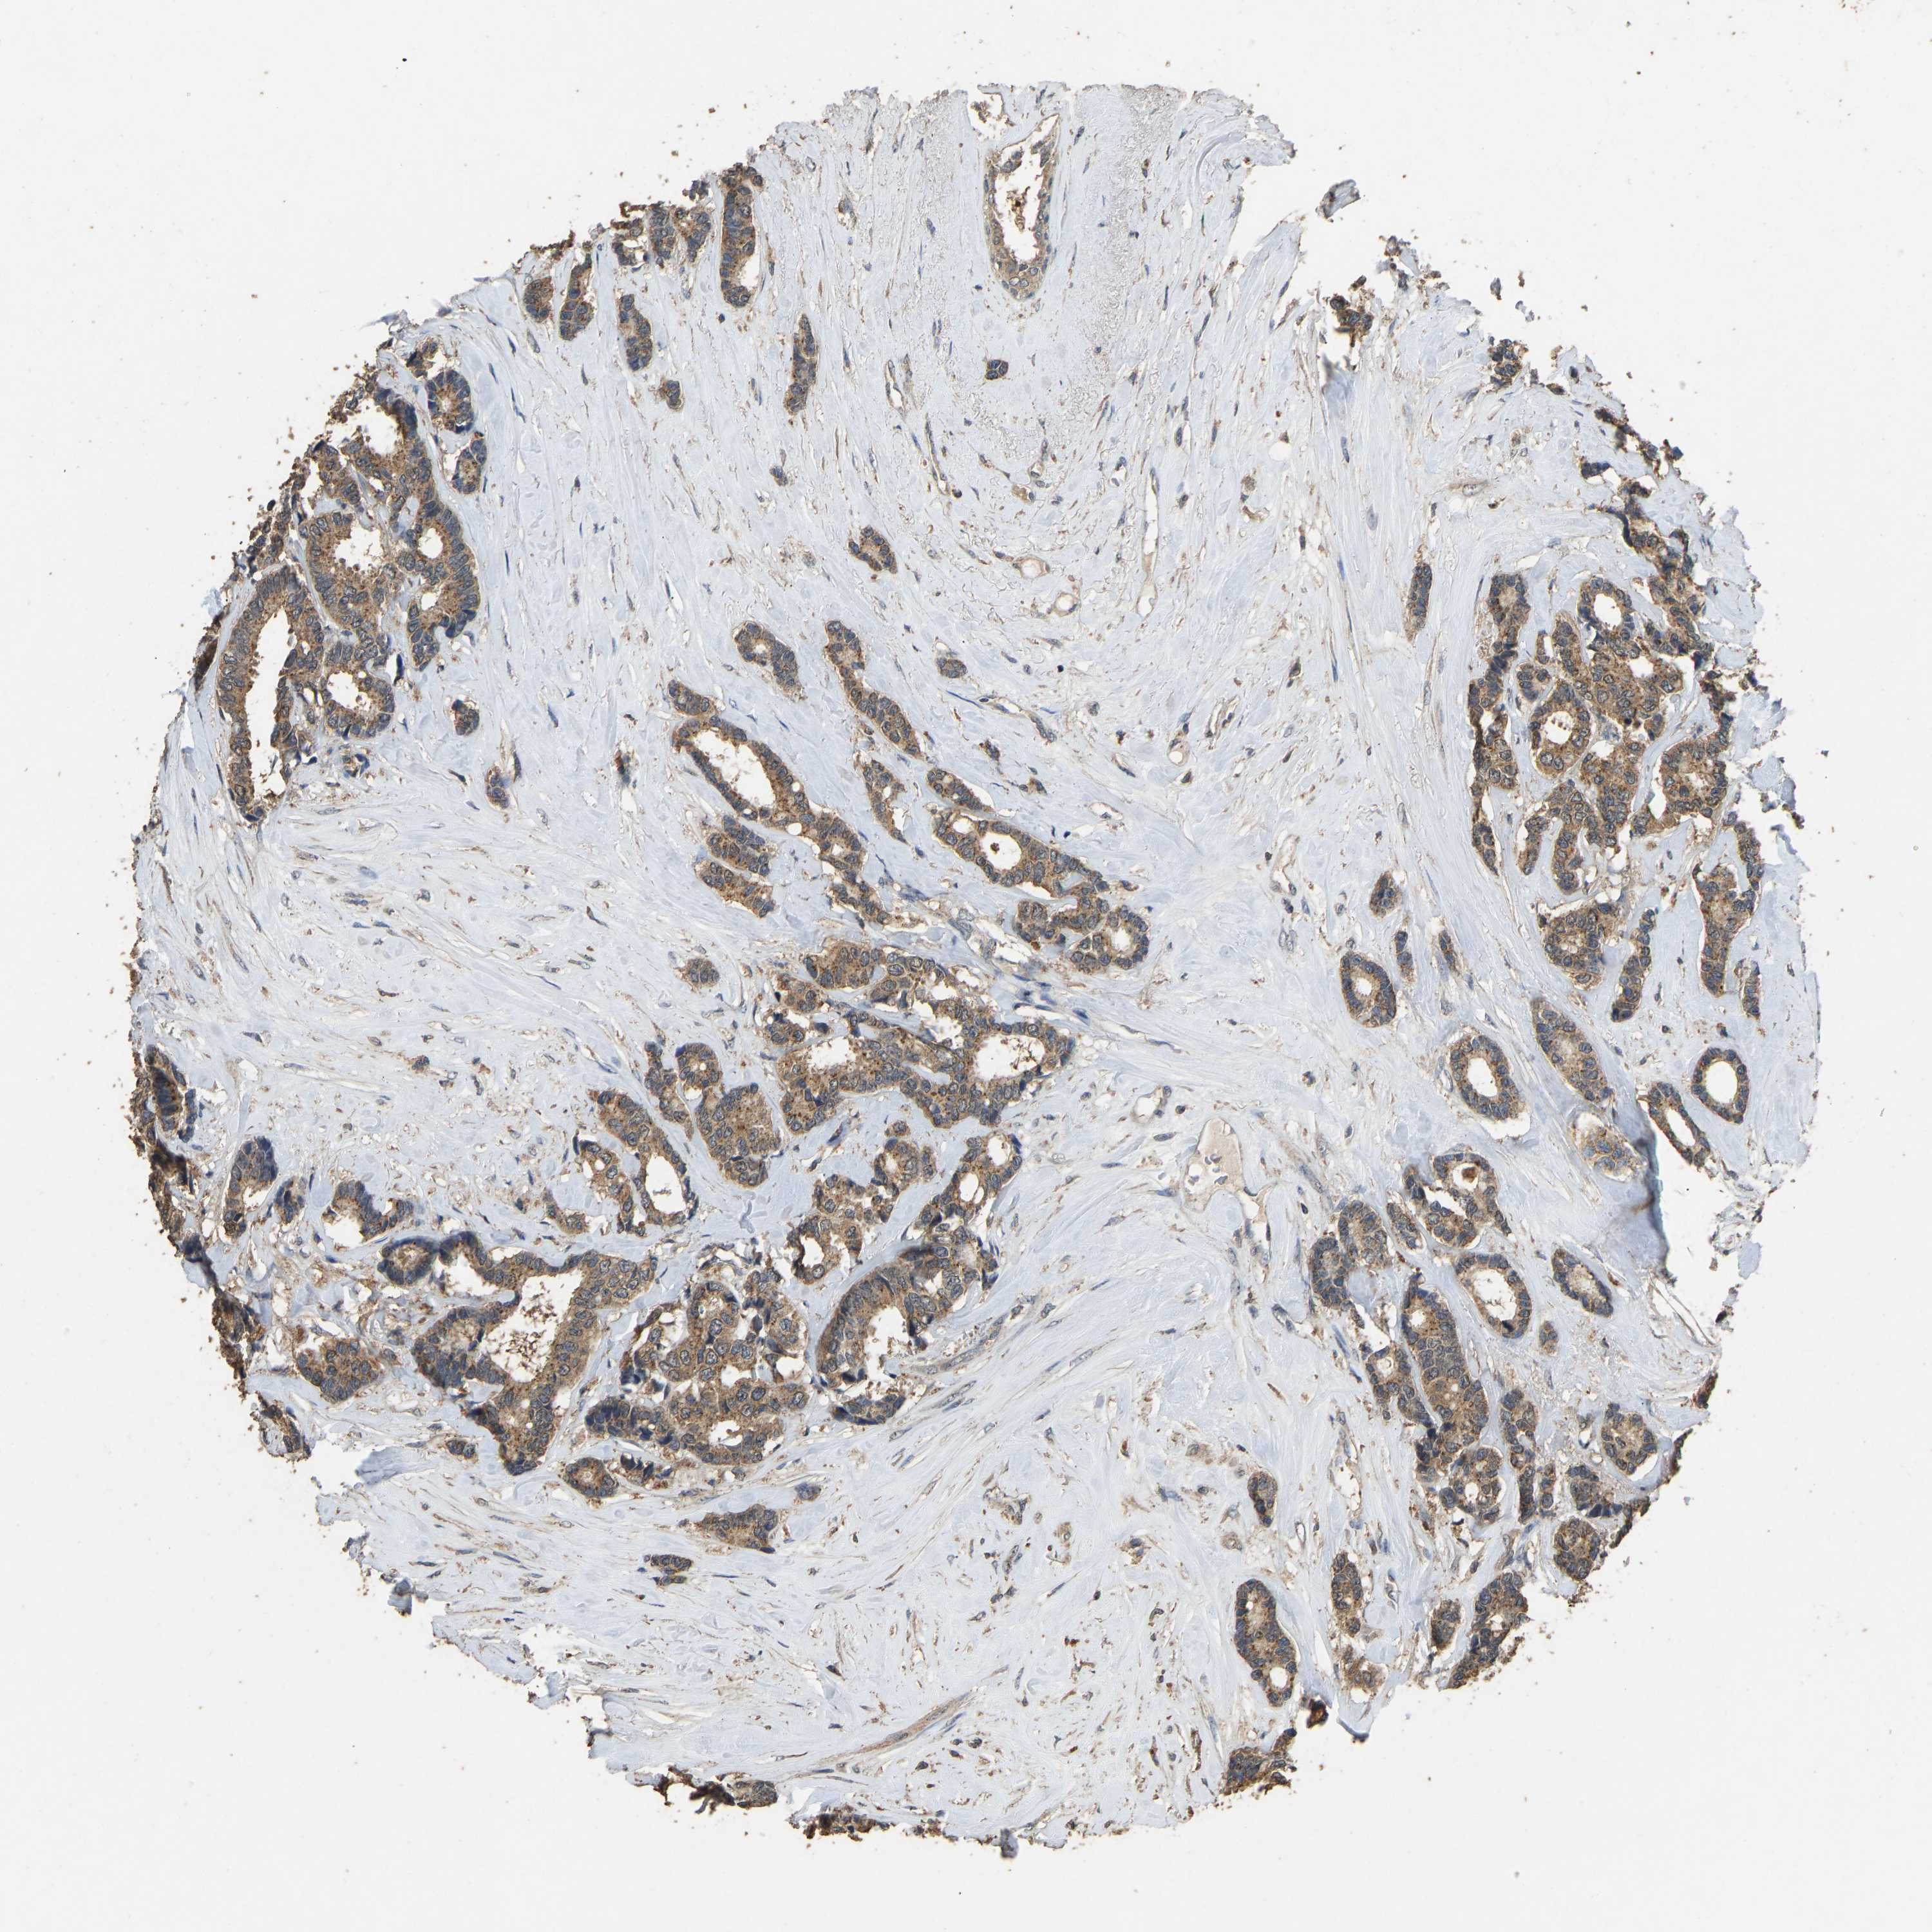

CANCER BREAST CANCER Show tissue menu

BRCA TCGA BRCA VALIDATION PROTEIN EXPRESSION